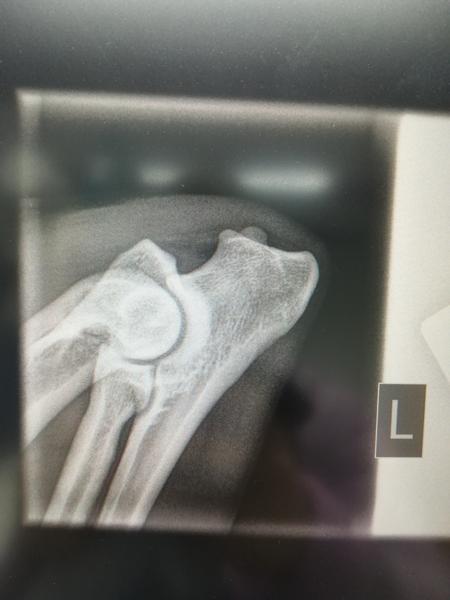

Til dem, der kan lide at vurdere HD/AD billeder {{forumTopicSubject}}

Iza's HD/AD billeder fra i dag.

Hvis nogen er glade for at vurdere den slags, er de velkomne med et bud.

Jeg skal nok skrive svaret fra DKK, når det kommer.

Men tænker du får a på de der hofter.

Men vil så(lidt pessimistisk) sige B/A, men tror nok mest på A/A.. Albuer har jeg ikke en anelse om, men de ser ud til at passe sammen, som de andre så fint siger også

Albuer 0

Iza's status kom i dag: HD A, AD 0